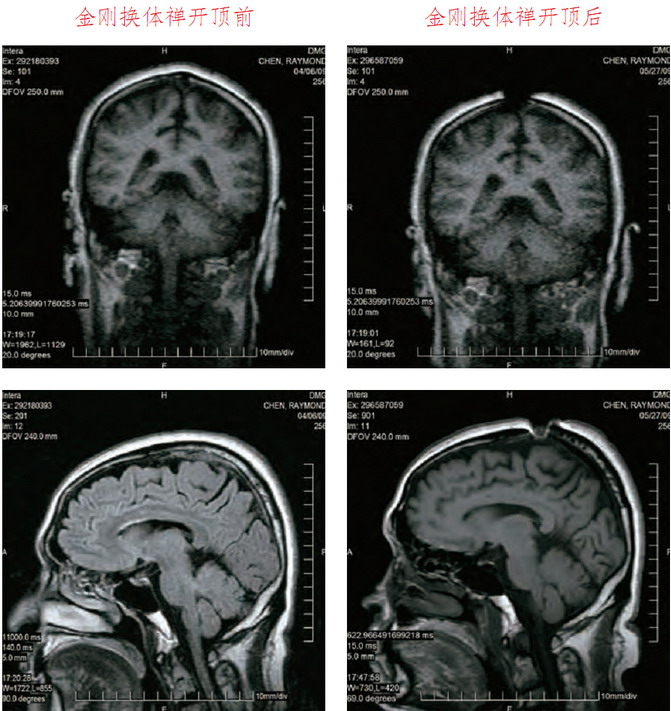

这是禄东赞法王修境行法“金刚换体禅”前后,MRI核磁共振仪脑断层扫瞄检测照片。可以清楚看见,开顶后,头顶大乐轮门处的头骨、皮层和肉、脑髓裂开约一英吋宽。

禄东赞尊者第四世慈仁嘉措法王开顶成就医学图片对比